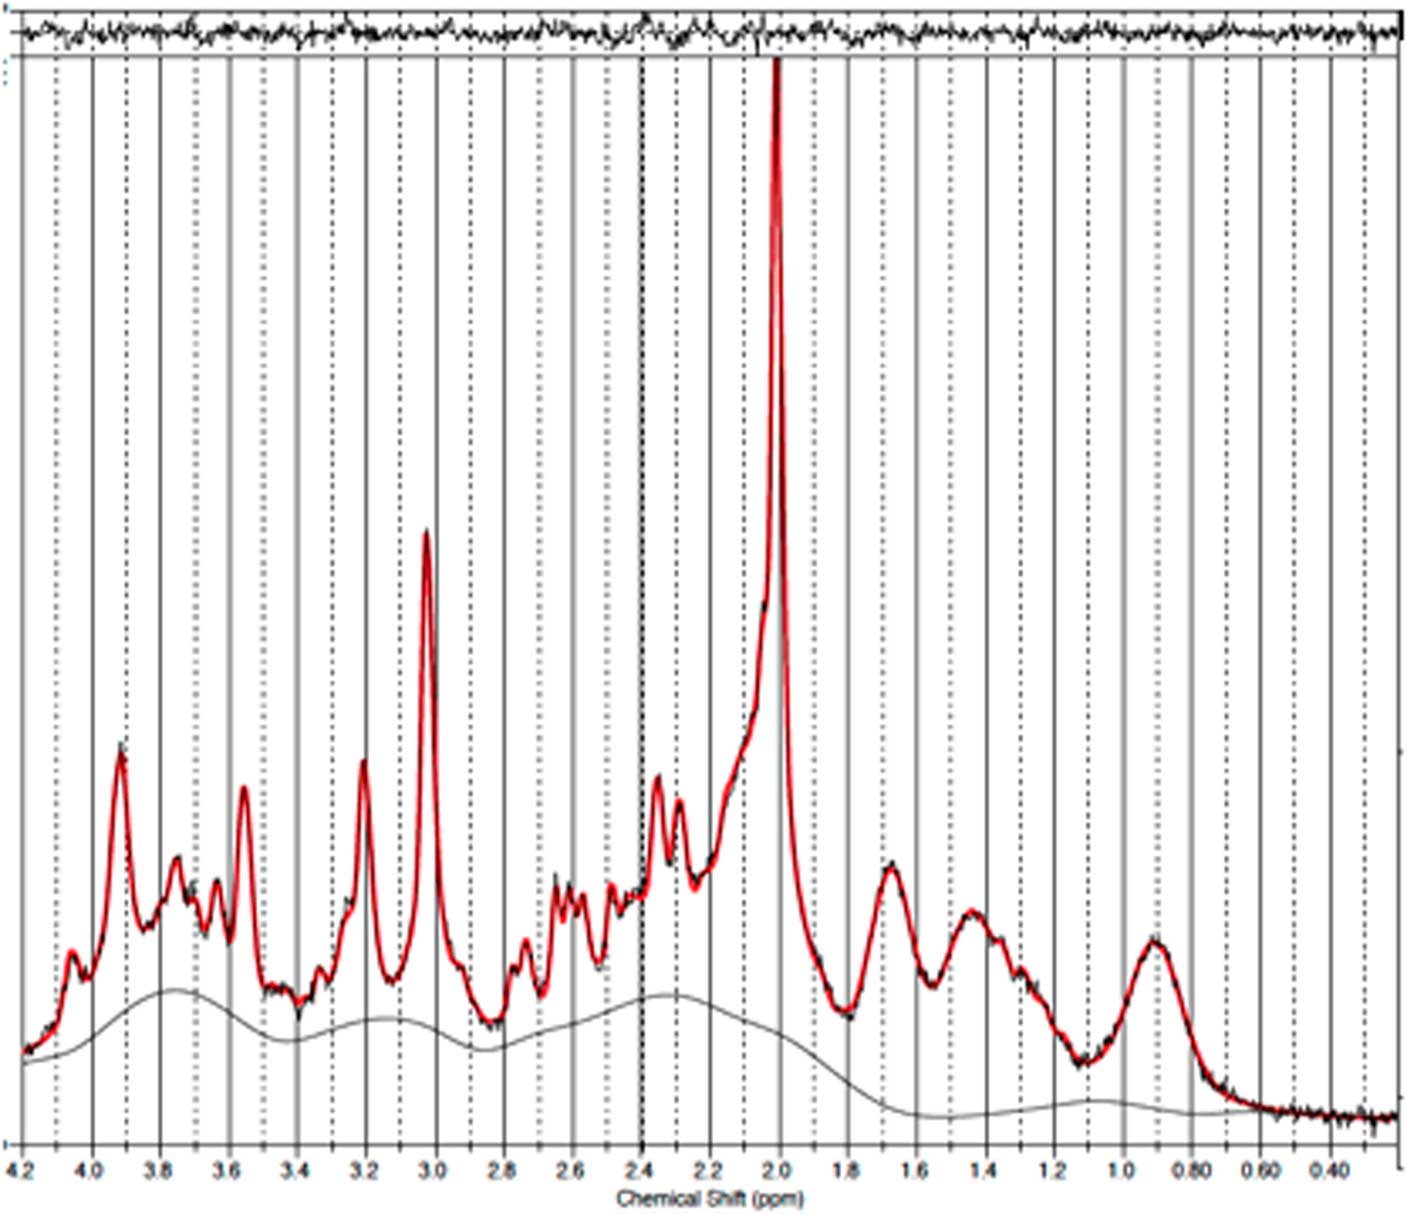

GABA measurements in PFC

Baseline and follow-up data were collected from all 11 patients. However, prefrontal spectra from one patient (male) and one healthy subject (male) were discarded due to poor quality (CRLB>20%). Figure 2 illustrates representative spectra from PFC and Fig. 3 an individual plot for the GABA signal in PFC. No significant difference in prefrontal GABA levels was observed between patients pre-ECT (mean 0.248±0.04) and healthy subjects (mean 0.249±0.03), t(20)=0.089, p=0.93 (Fig. 4). To examine whether GABA/Cr ratios were affected by changes in creatine, we tested for significant differences in GABA/NAA ratios (p=0.92) and NAA/Cr ratios (p=0.99), but no significant difference was found. Diagnosis, that is bipolar disorder or MDD did not interact significantly with the GABA/Cr ratio (p=0.75). Moreover, we found no significant changes in GABA/Cr ratio after excluding patients receiving benzodiazepines.

Fig. 2 Example of a representative spectrum from the prefrontal cortex. The raw data are plotted as a thin black curve. The thick red curve is the LcModel fit to this data. The baseline is also plotted as a thin black curve. At the top are plotted the residuals.